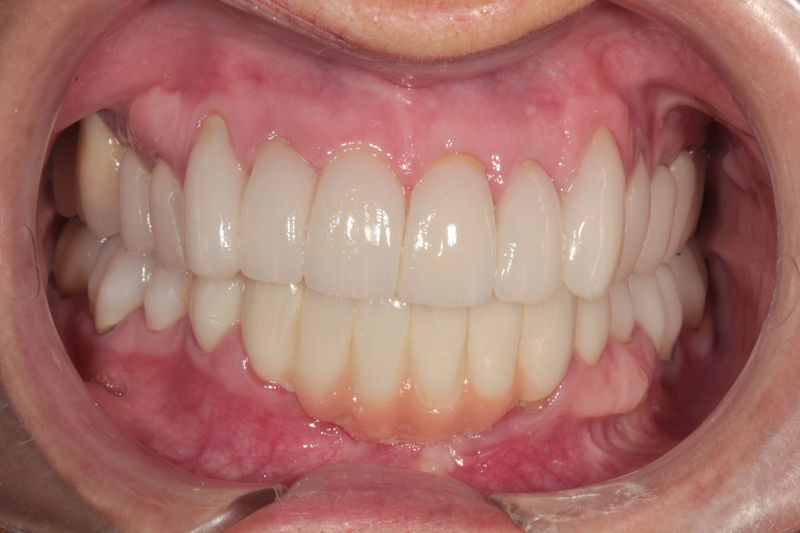

Amplia gama de tratamientos para mejorar la apariencia de la sonrisa, corrigiendo el color, la forma, el tamaño, la alineación y la posición de los dientes. Los procedimientos más comunes y solicitados incluyen el blanqueamiento dental, las carillas y coronas, así como las resinas.

Restauraciones fabricadas en el laboratorio con materiales estéticos, los cuales cubren de manera total dientes anteriores y posteriores. Se utilizan primariamente para restaurar dientes con caries, fracturas y/o defectos amplios, así como soportes de puentes. Para poder enviar el caso al laboratorio se toman impresiones utilizando materiales de impresión o técnicas modernas digitales.

Implantes, ortodoncia y coronas.